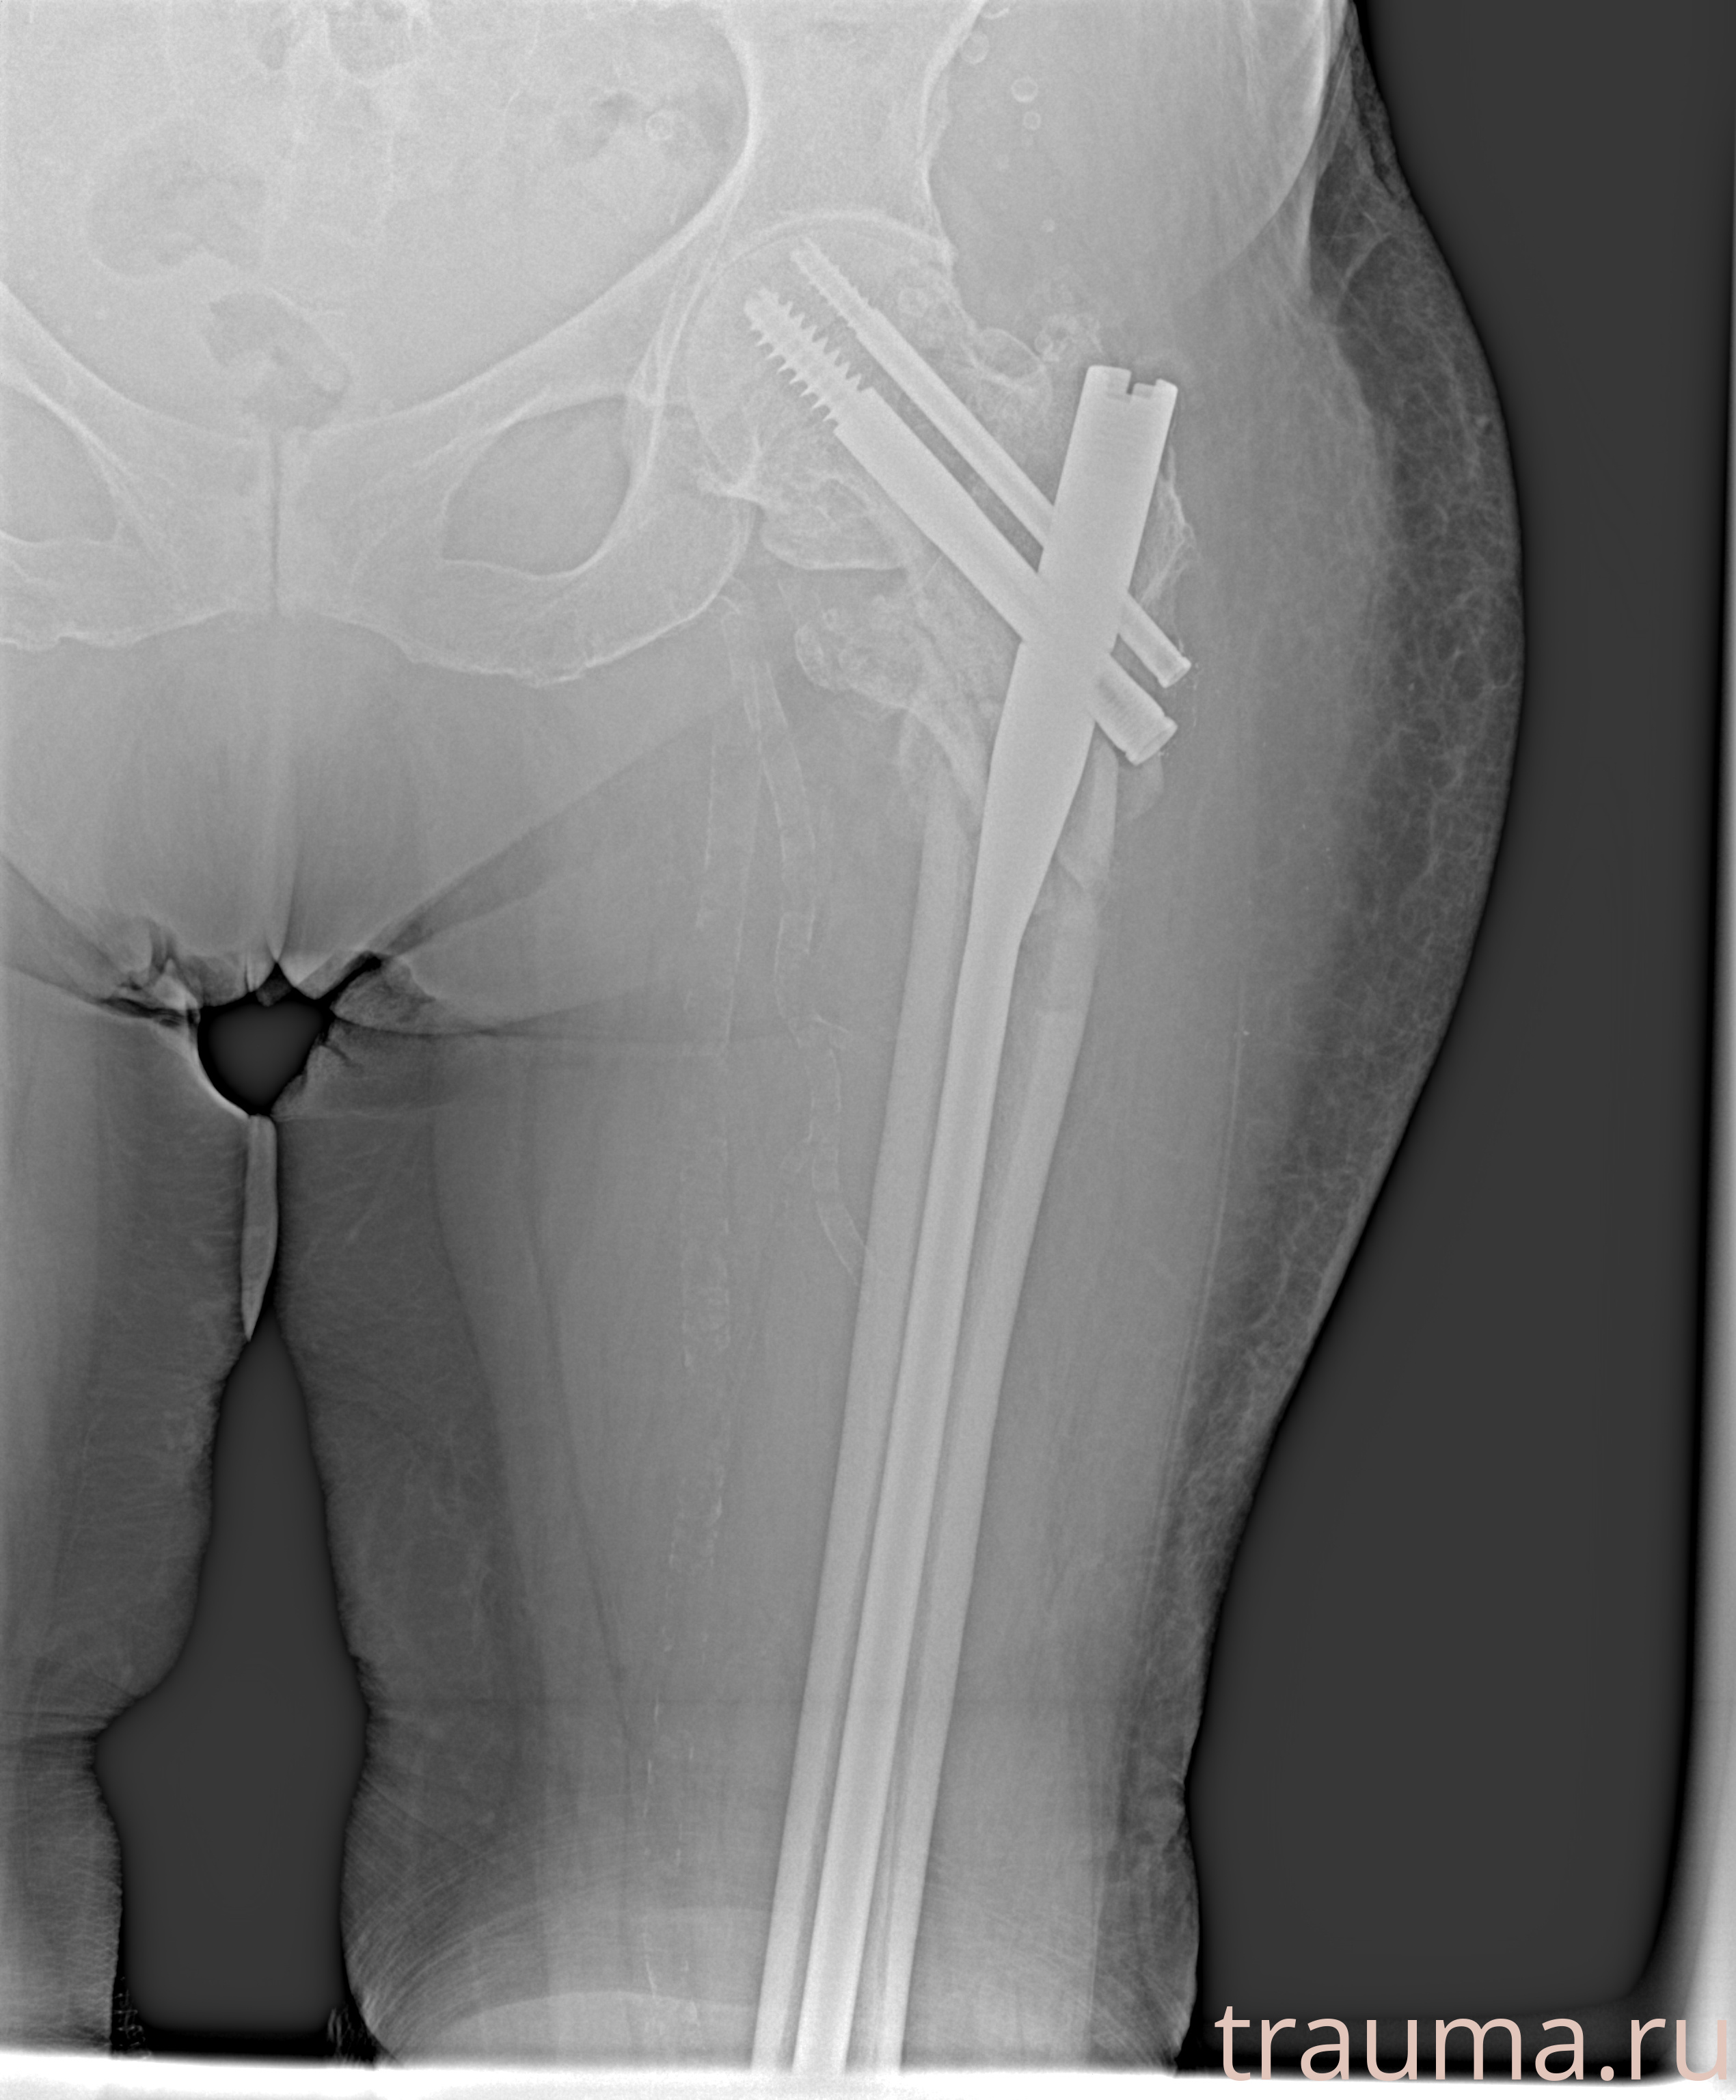

Рентгенограммы

Рентген на дому: по вашему адресу приезжает врач-рентгенолог, травматолог-ортопед с мобильным рентгеновским аппаратом, проводит диагностику травмы или заболевания, делает необходимые рентгенограммы, дает рекомендации по дальнейшему лечению. Получить качественные снимки в домашних условиях возможно благодаря уникальной методике, разработанной МосРентген Центром для института  Склифосовского